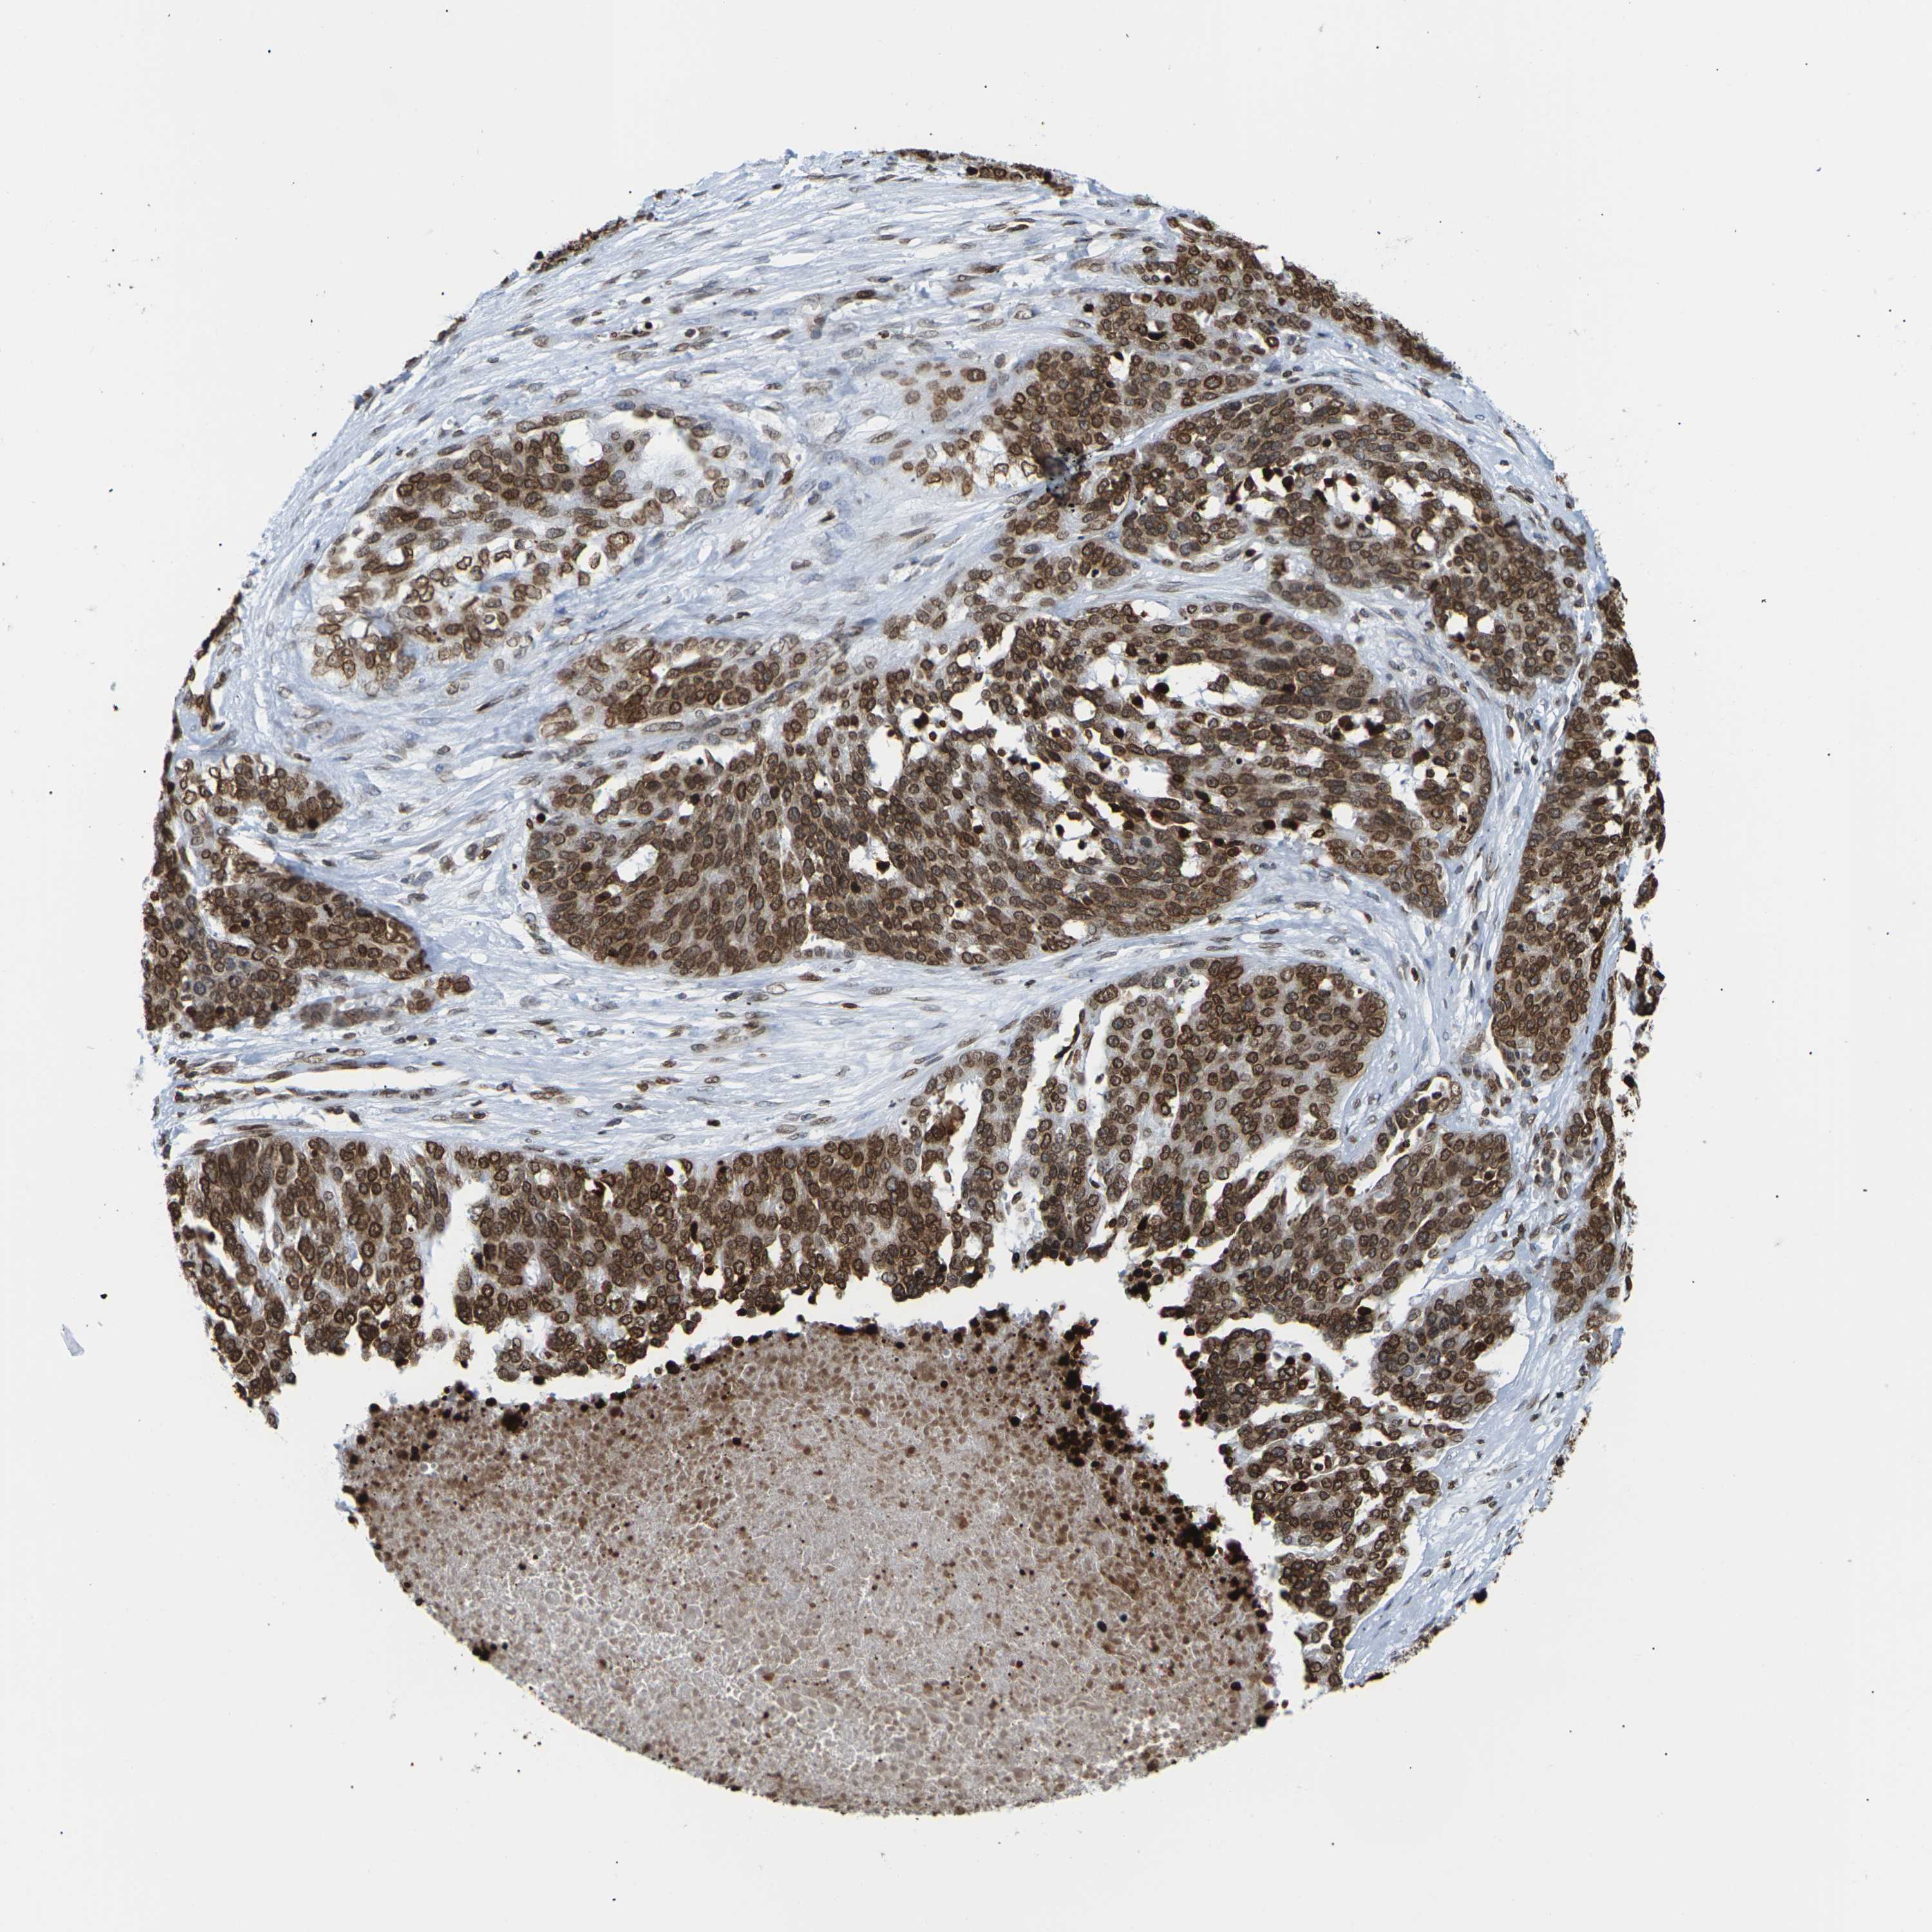

OVARIAN CANCER - Protein expressioni

A mouse-over function shows sample information and annotation data. Click on an image to view it in a full screen mode. Samples can be filtered based on level of antibody staining by selecting one or several of the following categories: high, medium, low and not detected. The assay and annotation is described here.

Note that samples used for immunohistochemistry by the Human Protein Atlas do not correspond to samples in the TCGA dataset.

Antibody stainingi

Antibody staining in the annotated cell types in the current human tissue is reported as not detected, low, medium, or high, based on conventional immunohistochemistry profiling in selected tissues. This score is based on the combination of the staining intensity and fraction of stained cells.

Each image is clickable and will lead to virtual microscopy that enables deeper exploration of all samples and also displays staining intensity scores, fraction scores and subcellular localization as well as patient and tissue information for each sample.

Antibody HPA041189

Antibody CAB011483

Staining

High

Medium

Low

Not detected

Intensity

Strong

Moderate

Weak

Negative

Quantity

>75%

75%-25%

<25%

None

Location

Nuclear

Cytoplasmic/membranous

Cytoplasmic/membranous,nuclear

Cystadenocarcinoma, serous, NOS

Carcinoma, endometroid

Cystadenocarcinoma, mucinous, NOS

Carcinoma, NOS